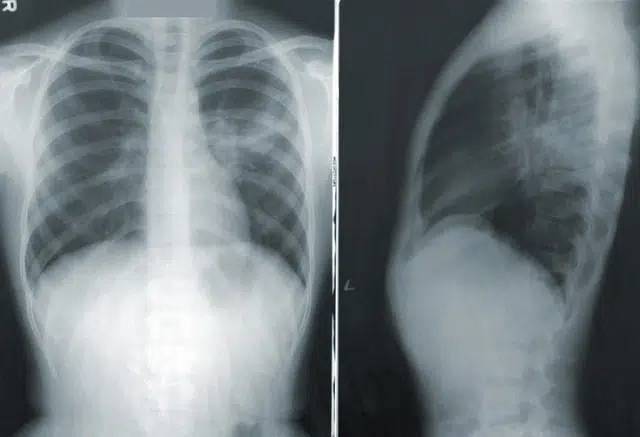

सार्कोडोसिस एक ऐसी बीमारी है जिसमें शरीर के विभिन्न अंगों (आमतौर पर फेफड़े और लिम्फ नोड्स) में सूजन पैदा करने वाली कोशिकाओं (ग्रैनुलोमा) के छोटे-छोटे गुच्छे बढ़ जाते हैं, जिससे सूजन हो जाती है। प्रभावित अन्य हिस्सों में आंखें, त्वचा, हृदय, यकृत, मस्तिष्क, गुर्दे, हड्डियां, मांसपेशियां, जोड़ और प्लीहा शामिल हैं। सार्कोडोसिस के लिए होम्योपैथी को सहायक उपचार के रूप में माना जाना चाहिए।

कई मामलों में कोई संकेत या लक्षण उत्पन्न नहीं होते। जब ये होते हैं तो यह इस बात पर निर्भर करता है कि कौन सा अंग इससे प्रभावित है। कुछ मामलों में लक्षण धीरे-धीरे विकसित होते हैं और कई वर्षों तक बने रहते हैं। जबकि अन्य मामलों में लक्षण अचानक उभरते हैं और जल्दी ठीक भी हो जाते हैं। वैसे सामान्य लक्षणों में थकान, वजन कम होना, दर्दनाक जोड़ों में सूजन और लिम्फ नोड्स में सूजन शामिल हैं। जब फेफड़े प्रभावित होते हैं तो उत्पन्न होने वाले लक्षणों में सूखी खांसी, सीने में दर्द, घरघराहट और सांस की तकलीफ शामिल हैं। जब यह आंखों को प्रभावित करता है तो जो संकेत और लक्षण दिखाई दे सकते हैं उनमें आंखों में दर्द, दृष्टि का धुंधलापन, आंखों का लाल होना, सूखी आंखें, आंखों में खुजली, आंखों में जलन और प्रकाश के प्रति संवेदनशीलता शामिल हैं।